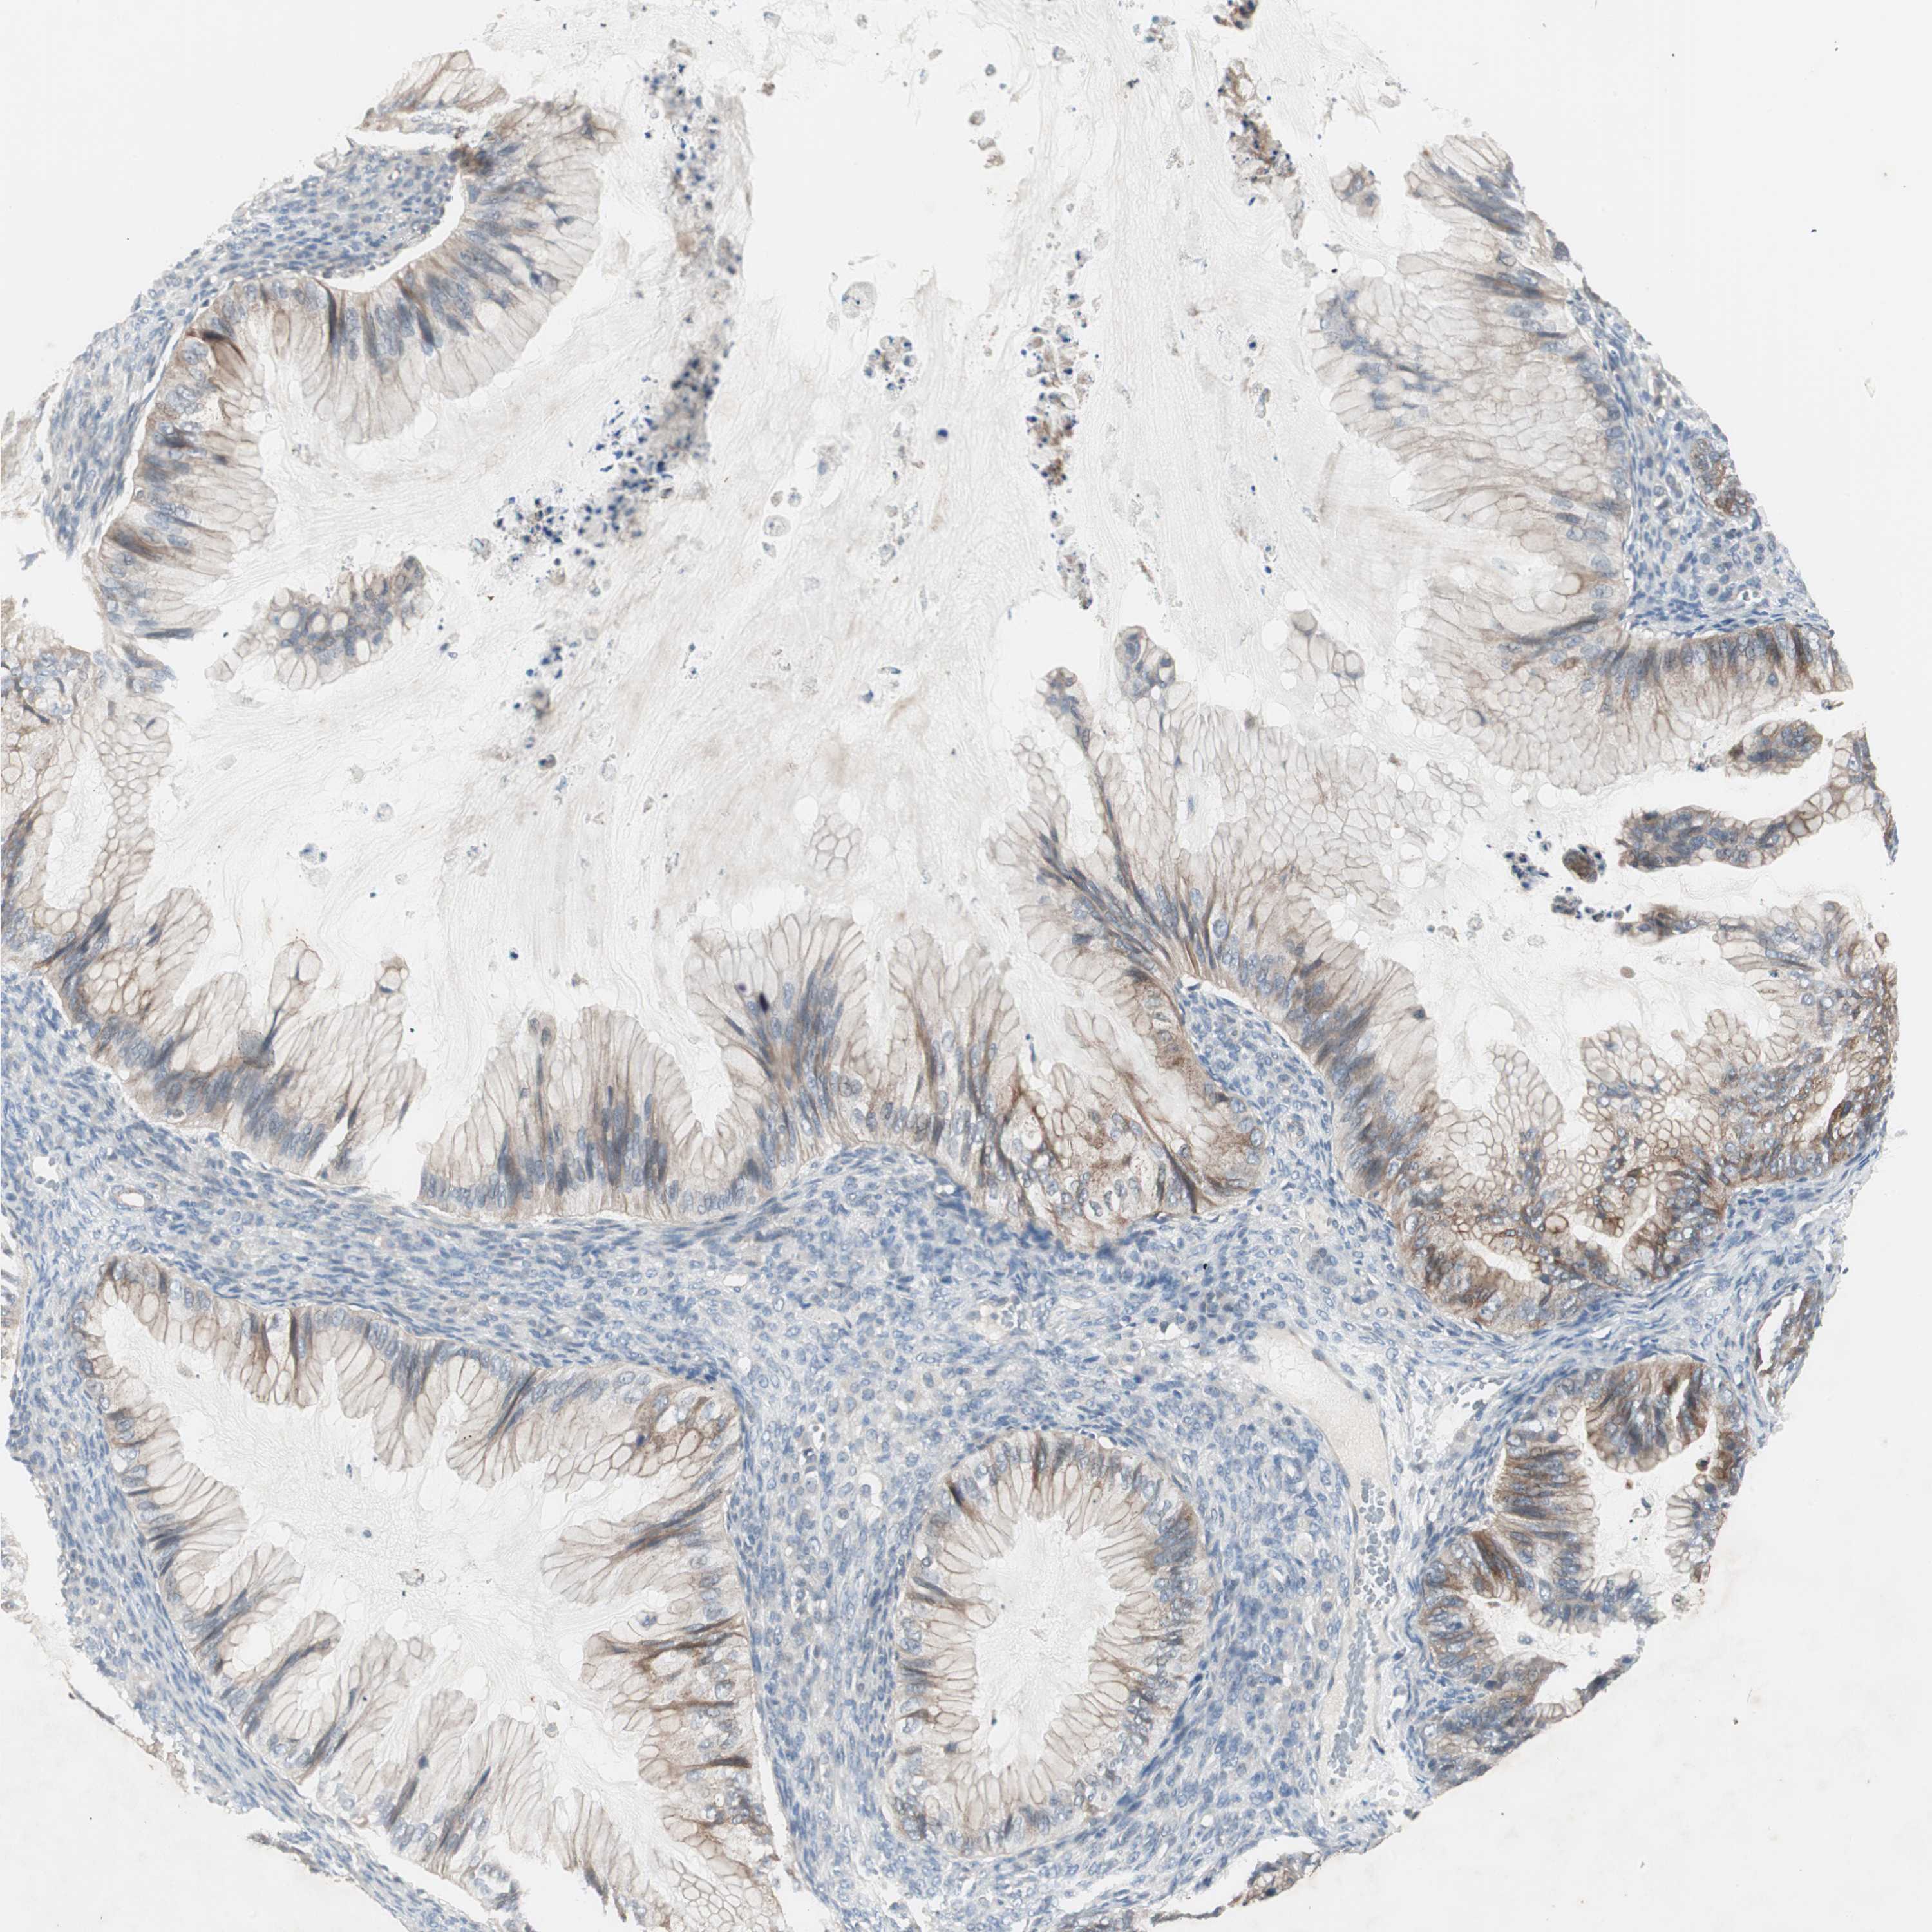

OVARIAN CANCER - Protein expressioni

A mouse-over function shows sample information and annotation data. Click on an image to view it in a full screen mode. Samples can be filtered based on level of antibody staining by selecting one or several of the following categories: high, medium, low and not detected. The assay and annotation is described here.

Note that samples used for immunohistochemistry by the Human Protein Atlas do not correspond to samples in the TCGA dataset.

Antibody stainingi

Antibody staining in the annotated cell types in the current human tissue is reported as not detected, low, medium, or high, based on conventional immunohistochemistry profiling in selected tissues. This score is based on the combination of the staining intensity and fraction of stained cells.

Each image is clickable and will lead to virtual microscopy that enables deeper exploration of all samples and also displays staining intensity scores, fraction scores and subcellular localization as well as patient and tissue information for each sample.

Antibody HPA036348

Antibody HPA036349

Antibody CAB002422

Antibody CAB005258

Cystadenocarcinoma, serous, NOS

Carcinoma, NOS

Cystadenocarcinoma, mucinous, NOS

Carcinoma, endometroid